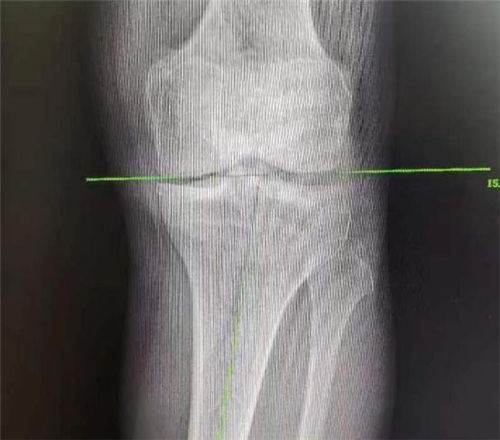

而近期患者感觉其左膝关节疼痛逐渐加重,伴随肿胀,甚至需要扶拐前行。因为患者对第一次手术效果非常满意,所以再次来到我院骨一科就诊。李强主任团队针对患者具体病情进行评估,发现患者负重位X线片显示左膝关节内侧间隙变窄,胫骨内翻,胫骨近端后倾角 76°,胫骨近端内侧角小于82°,左膝关节退行性改变。外侧间室及外侧关节间隙相对完好,测量后发现其畸形主要为关节内翻畸形。